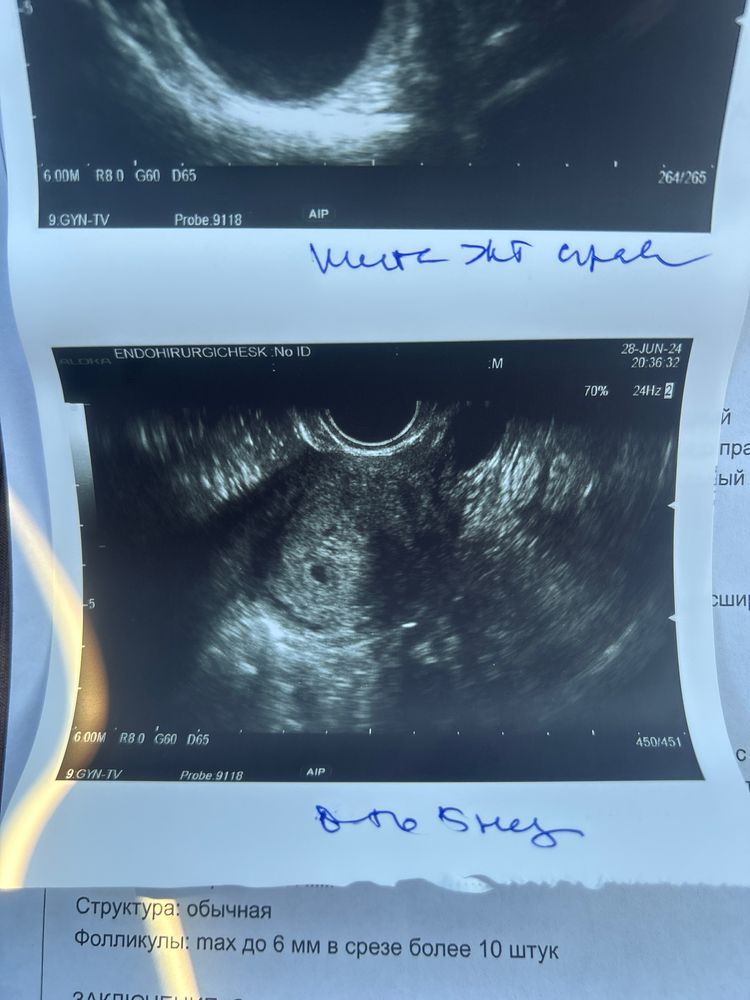

Полетела так рано на узи, потому что начались сильные боли в правом яичнике, отдающие в ногу. Конкретные такие. Со страху подумала, что внематочная. Шла туда готовая ко всему. А нет, это огромное жт 45х47 ☺️

по узи срок 5 недель ( я так и предполагала, что овуляция была 6-7 июня, почувствовала ее)